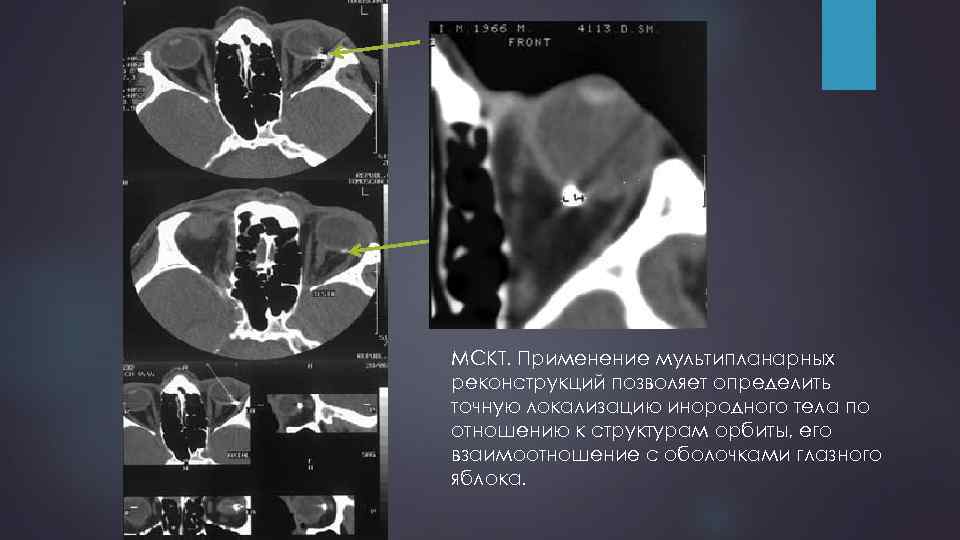

Инородные тела

МСКТ. Применение мультипланарных реконструкций позволяет определить точную локализацию инородного тела по отношению к структурам орбиты, его взаимоотношение с оболочками глазного яблока.